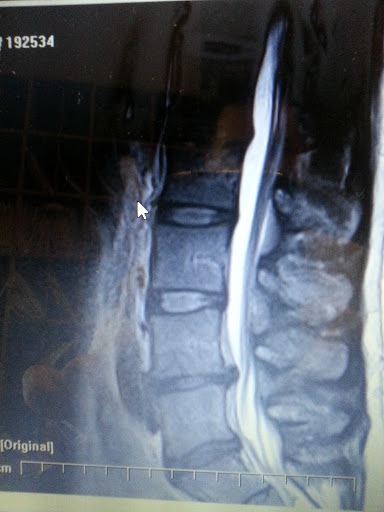

Category: Chiropractor

Dr Ulibarri knows the art of Chiropractic and applies it successfully to all types of injury, specializing in sports related injuries.